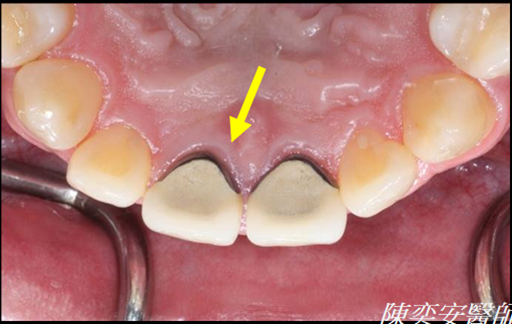

牙周再生手術(填補骨粉及再生膜)